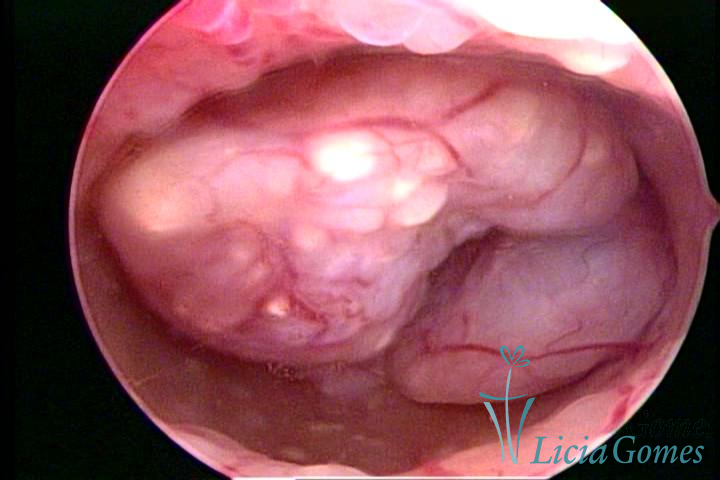

Este pode apresentar uma gama variável de aspectos macroscópicos, com aspecto pseudopolipoide; lembrando tecido cerebroide ou com reação deciduoide;a vascularização superficial é mais evidente e com vasos em formatos de saca-rolha ou espirais visualizando também a vascularização com atípias, com aumento do calibre dos vasos superficiais, pode ser encontrado também tecido em necrose, poderá haver um pequenos dendritos (papilomatoso).